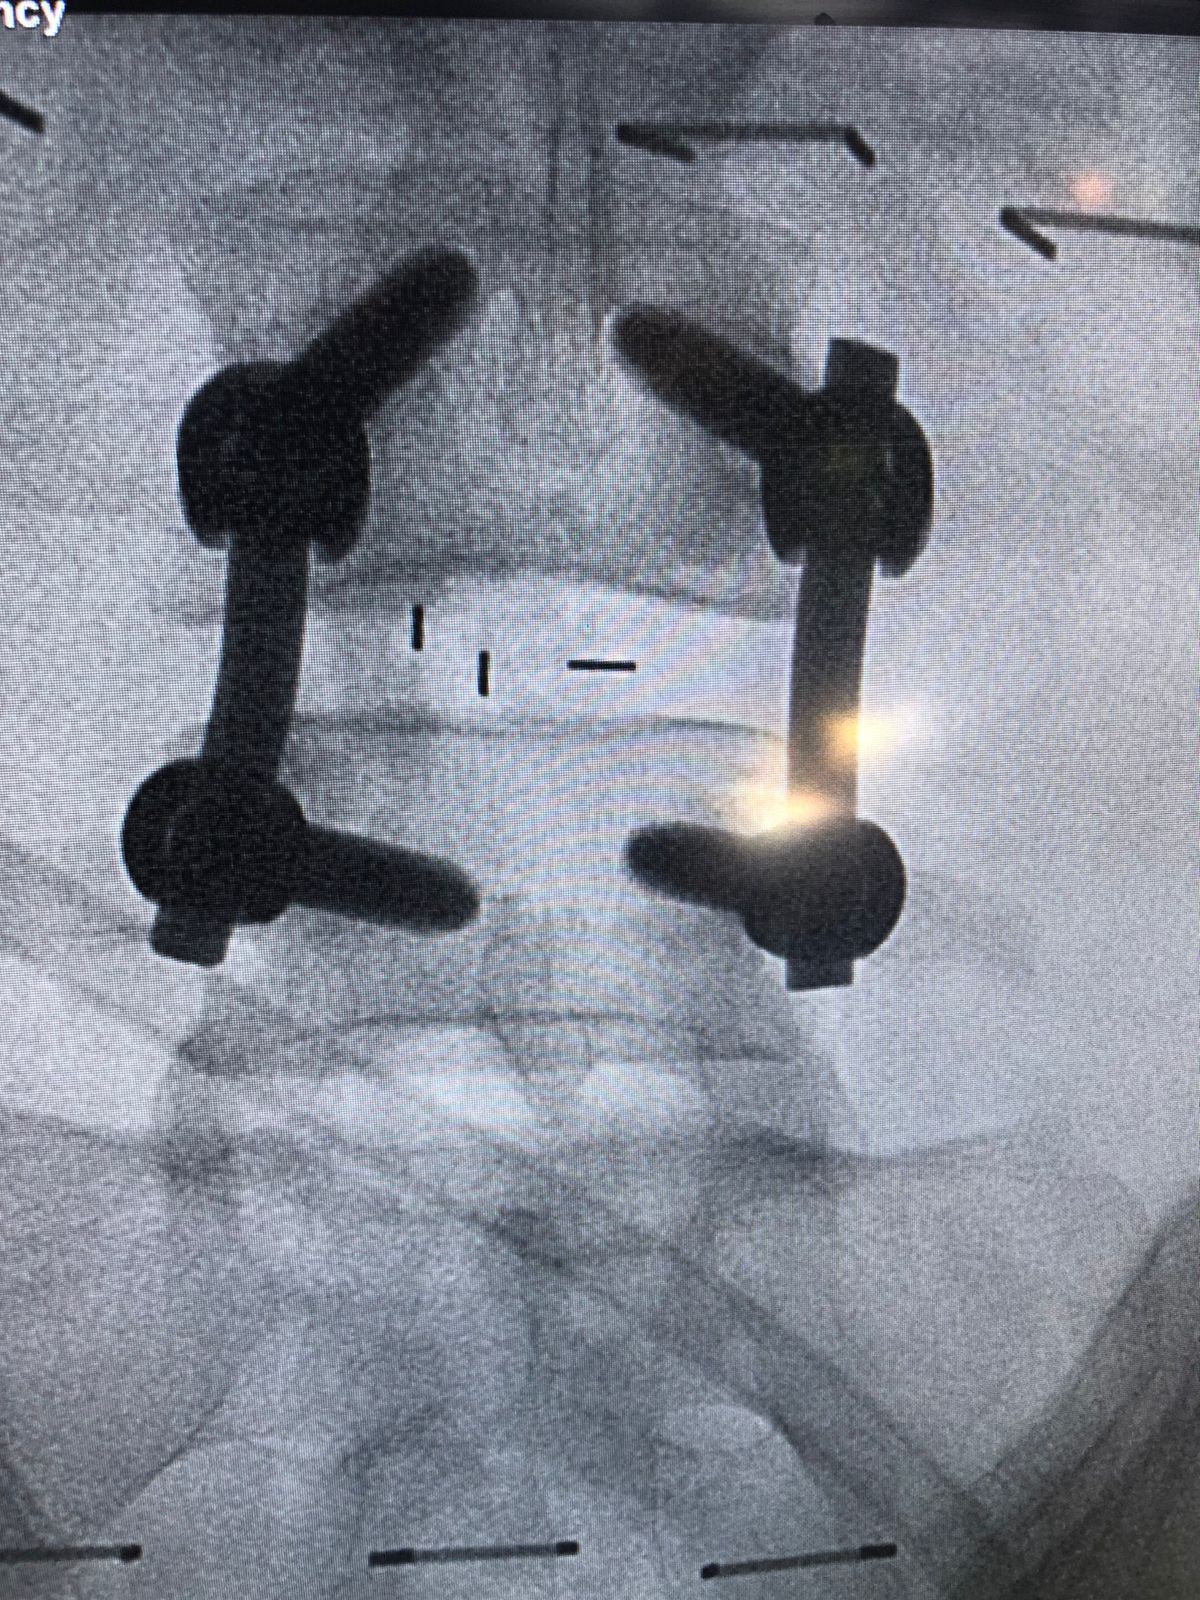

وأوضح د. متعب أبوالراس أن تفاصيل الحالة للمريضة كانت تشكو من آلام مزمنة في الظهر وتمتد إلى الأطراف السفلية مما تؤدي إلى إعاقة قدرتها عن الحركة أو حتى الوقوف، وبعد عمل الفحص الإكلينيكي والأشعة اللازمة تبيّن أن المريضة تعاني من "حالة إنزلاق فقاري مصحوب بإنزلاق غضروفي وضيق في القناة العصبية بين الفقرتين الرابعة والخامسة القطنية" مع ضرورة التدخل الجراحي.

وأضاف د. أبو الراس بأنه تم إجراء العملية الدقيقة بعد موافقة المريضة عليها وعلى الخطة العلاجية ما بعدها، وتمثلت العملية في توسيع القناة العصبية واستئصال الغضروف ووضع دعامة بين الفقرات مع تصحيح الإنزلاق الفقاري وعمل دمج بين الفقرتين الرابعة والخامسة، وتكللت العملية بالنجاح -ولله الحمد- واستطاعت المريضة المشي في أول يوم لها بعد إجراء العملية.